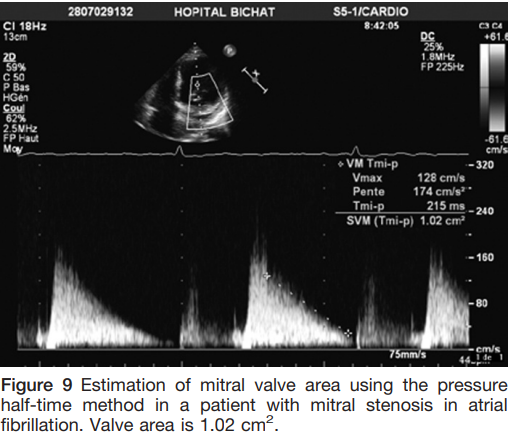

MVA Pressure half-time

- Time interval (in ms) between maximal mitral gradient in early diastole and the time-point when the gradient is half the maximal initial value

- The decline of the velocity of diastolic transmitral blood flow = inversely proportional to valve area

- MVA = 220 ⁄ T1⁄2

- Performed by tracing the deceleration slope of the E-wave on Doppler spectral display

- Avoid use in degenerative MS